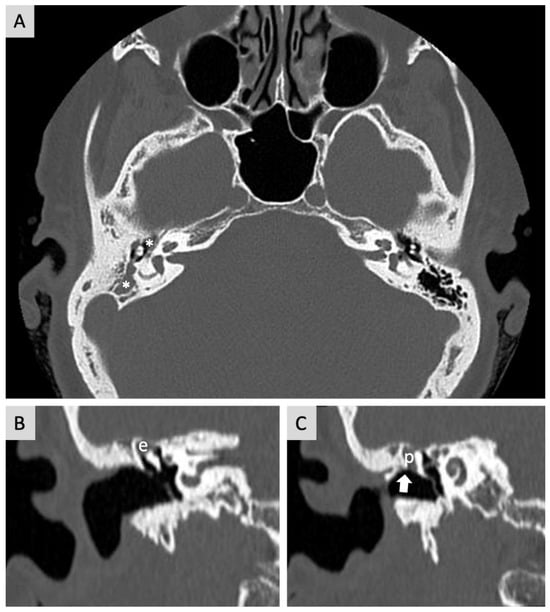

2. Case Report